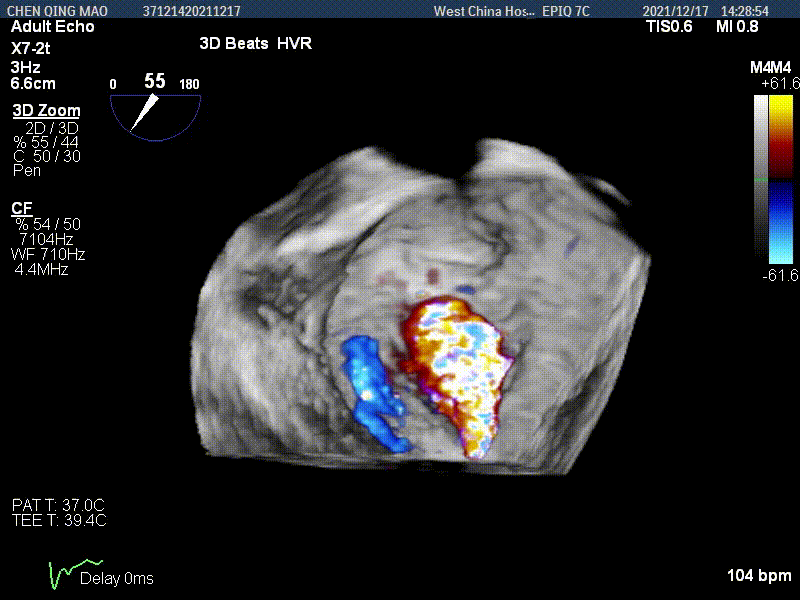

术后即刻超声评估